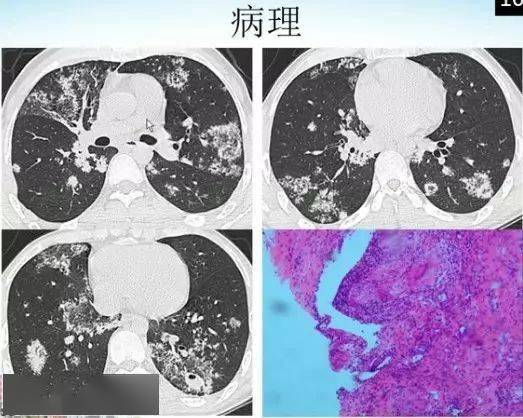

肺部烟花征的影像表现与鉴别诊断

胸部典型征象丨爆米花样钙化征

肺内爆米花样钙化病变!